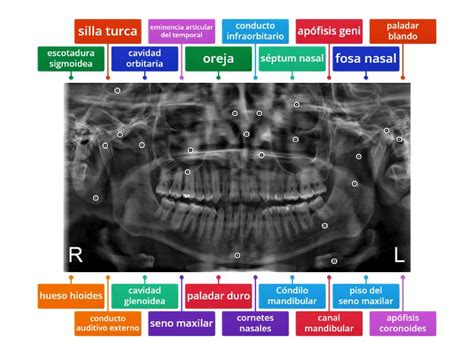

En el caso específico de la radiografía maxilar temporomandibular, se trata de una radiografía panorámica que muestra todos los dientes en una sola imagen. Esta técnica es crucial para localizar trastornos en la articulación que une la mandíbula con el cráneo, los cuales pueden impedir el correcto funcionamiento para alimentarse y hablar.

Es una técnica que utiliza rayos X para obtener imágenes de la articulación temporomandibular (ATM) con el fin de estudiarla. Esta articulación es fundamental para funciones como masticar, hablar y tragar. Las radiografías de la ATM pueden revelar problemas como:

La radiografía temporomandibular ayuda a los odontólogos a diagnosticar y planificar el tratamiento adecuado para los trastornos de la ATM.